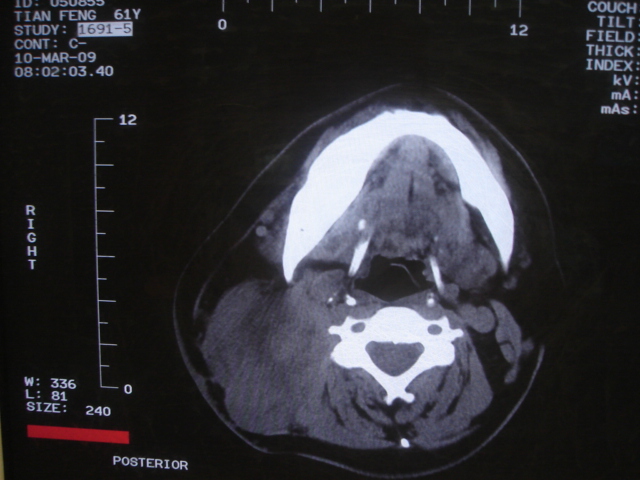

标题: CT18584:甲状腺Ca 喉转移?

患者 男 61  甲状腺ca术后7年 颈部淋巴结转移

声门下区表面不光整,增厚呈局限性突起,未见局部浸润.

考虑----颈部淋巴结转移,不排除---喉乳头状瘤可能.

颈部多个淋巴结增大,结合甲状腺ca术后7年病史考虑转移。

另声门区不规则突起,建议喉镜检查!

右侧颈部淋巴结转移,右声带乳头突起,乳头状瘤可能性大。

1)右侧颈部淋巴结转移瘤。2)右侧声带新生物,性质待定;建议喉镜检查(活检)。